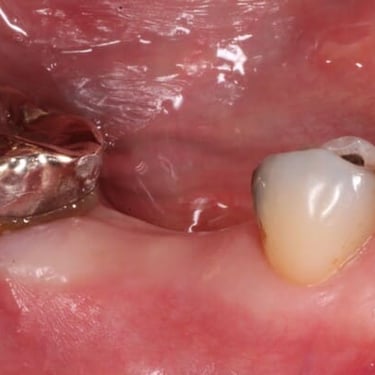

Implantes dentales fracasados

Los implantes dentales fracasados son aquellos que no se han integrado correctamente con el hueso o han desarrollado complicaciones postoperatorias.

Los pacientes pueden notar movilidad en el implante, dolor o inflamación.

El tratamiento puede incluir la extracción del implante fallido y la preparación para un nuevo implante.